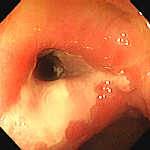

In faza de remisiune se repara epiteliul, cu formarea unei mucoase atrofice cu vascularizatie vizibila. Mai pot aparea pseudopolipi, dar nu exista sangerare si ulceratii. Exista forme cronice continue, cu fenomene de reparatie concomitente cu cele de distructie, ce duc la atrofia mucoasei rectale, cu aspect granular, hemoragii si ulcere. In formele tardive apar scurtari de colon si rect, ingustari de lumen colic si rectal, stergerea haustratiei colonice si o retractie sclerolipomatoasa. Toate acestea duc la microcolie si microrectie.

Remisiune-vase tortuoase, Remisiune- cicatrice liniare Pseudopolipi de regenerare

fara ramificatii